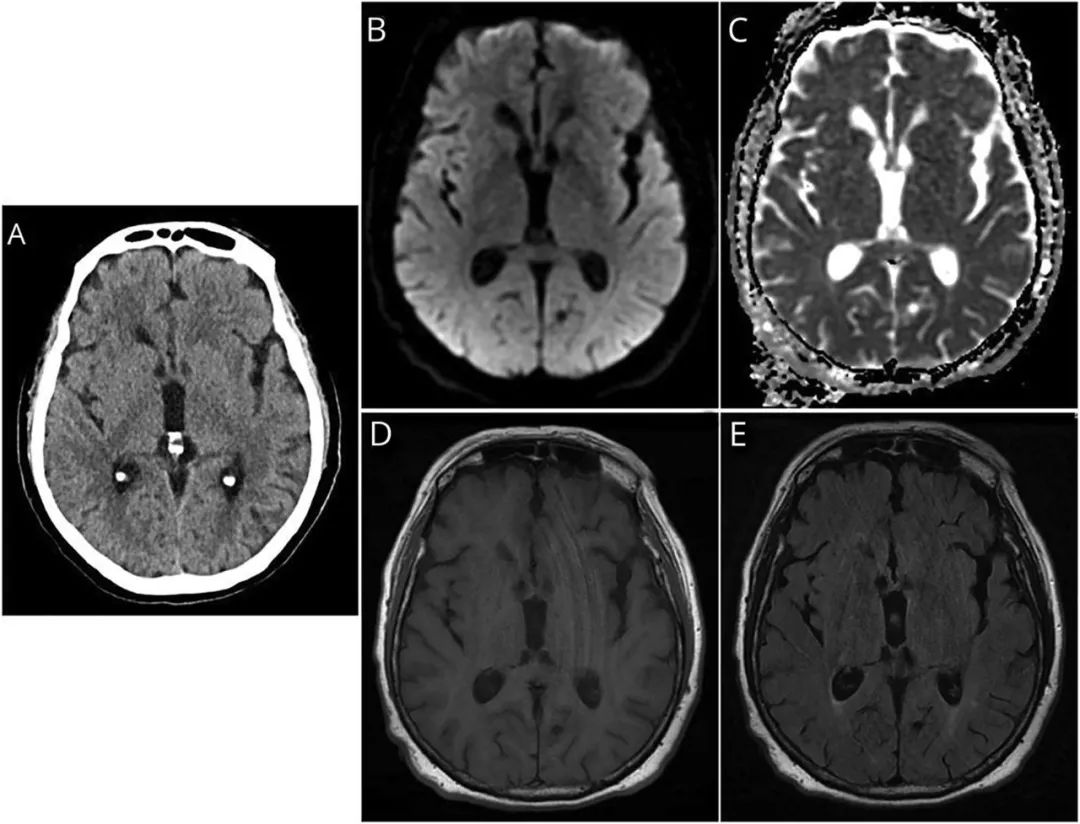

图1 入院时CT和MRI扫描结果

(A)首次入院时头部CT扫描显示轻度脑积水。患者在精神状态下降之前的弥散加权成像(B)、ADC影像(C)、FLAIR影像(D)和T1序列影像(E)。